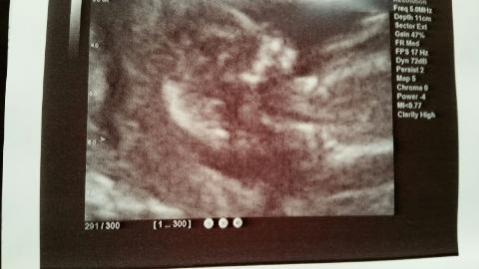

Hi ladies! I haven't been in here in a while and I have another baby on the way. (I didn't sway) I have 2 u/s one from last week at 12.5 and one from today at 13.5 please nub guess if you can or let me know if there is no nub (I'm not good at spotting them). TIA